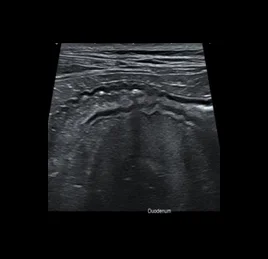

초음파 검사는 고주파 음파를 이용해 장기와 조직의 실시간 움직임을 영상으로 확인하는 비침습적 진단법입니다.

장기의 구조뿐 아니라 혈류, 운동성, 기능 변화까지 평가할 수 있어, 다양한 질환의 조기 발견과 모니터링에 효과적입니다.

📍초음파 진단 케이스

• 위장관염